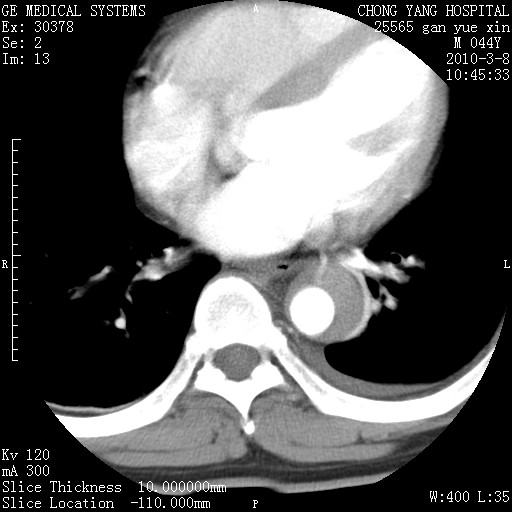

标题: CT24940:主动脉增强,典型病例。 [打印本页]

标题: CT24940:主动脉增强,典型病例。

夹层动脉瘤。

动脉夹层

夹层动脉瘤,典型

主动脉夹层。

动脉夹层的分型:

⒈debakey分型:根据主动脉夹层累及部位,分为三型:ⅰ型:原发破口位于升主动脉或主动脉弓部,夹层累及升主动脉、主动脉弓部、胸主动脉、腹主动脉大部或全部,少数可累及髂动脉。ⅱ型:原发破口位于升主动脉,夹层累及升主动脉,少数可累及部分主动脉弓。ⅲ型:原发破口位于左锁骨下动脉开口远端,根据夹层累及范围又分为ⅲa,ⅲb。ⅲa型:夹层累及胸主动脉。ⅲb型:夹层累及升主动脉、腹主动脉大部或全部。少数可累及髂动脉。

⒉stanford分型:a型:夹层累及升主动脉,无论远端范围如何。b型:夹层累及左锁骨下动脉开口以远的降主动脉。

夹层动脉瘤,少量胸水

夹层动脉瘤;左侧少量胸腔积液。

典型主动脉夹层。